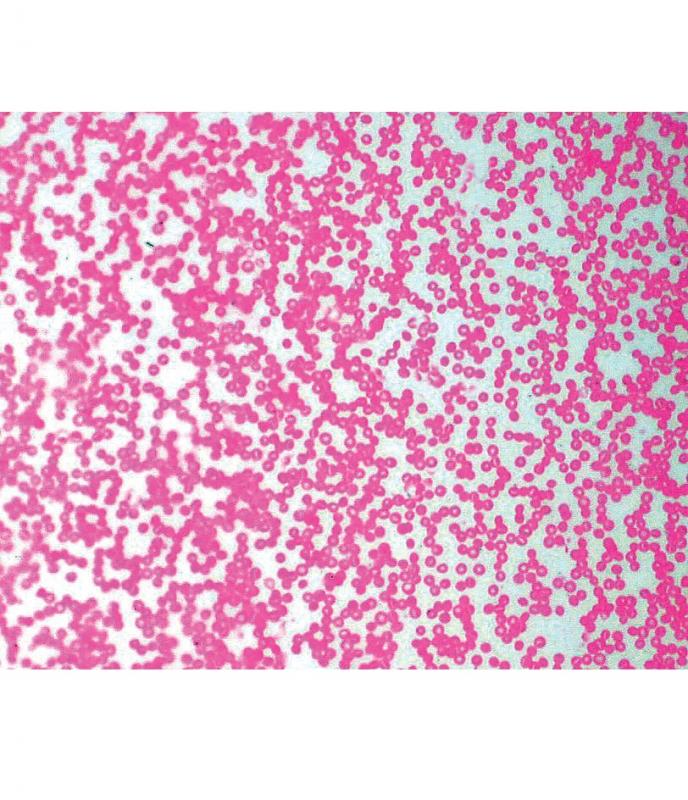

Préparation microscopique: Sang humain (giemsa)

Sang humain (Giemsa) Photos : Microscope BioBlue Objectif semi-plan : x4 et x10 Caméra Toupcam À l'unité